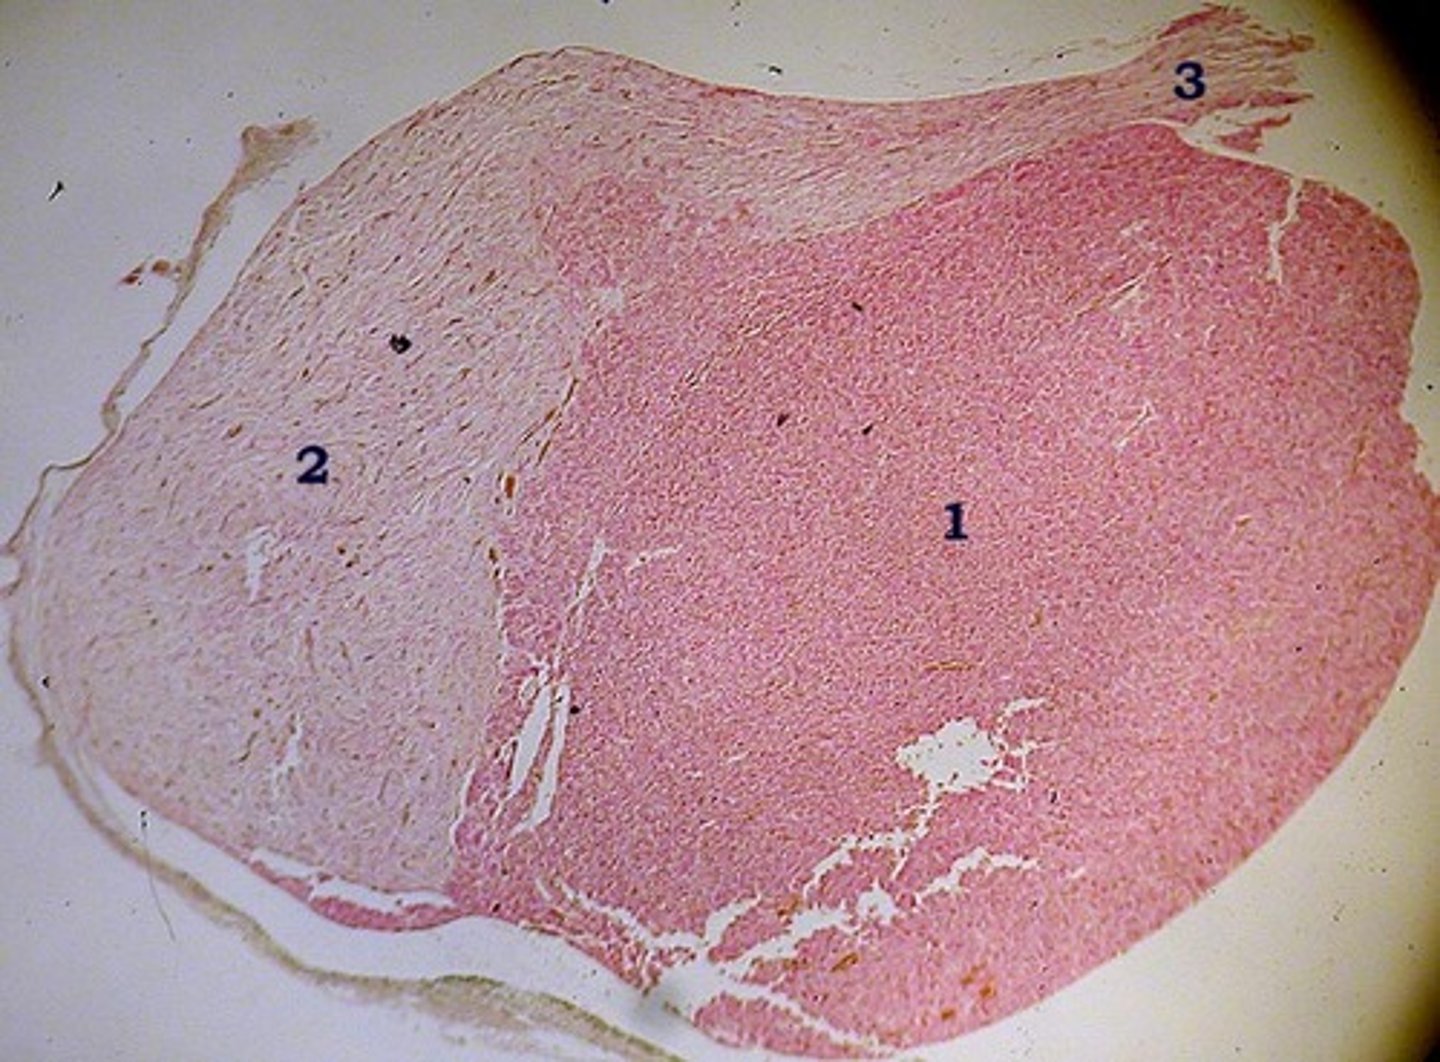

adrenal gland (suprarenal gland)

what organ is this

capsule of adrenal gland

1

zona glomerulosa of adrenal gland

2

zona fasciculata of adrenal gland

3

zona reticularis of adrenal gland

4

adrenal medulla of adrenal gland

5